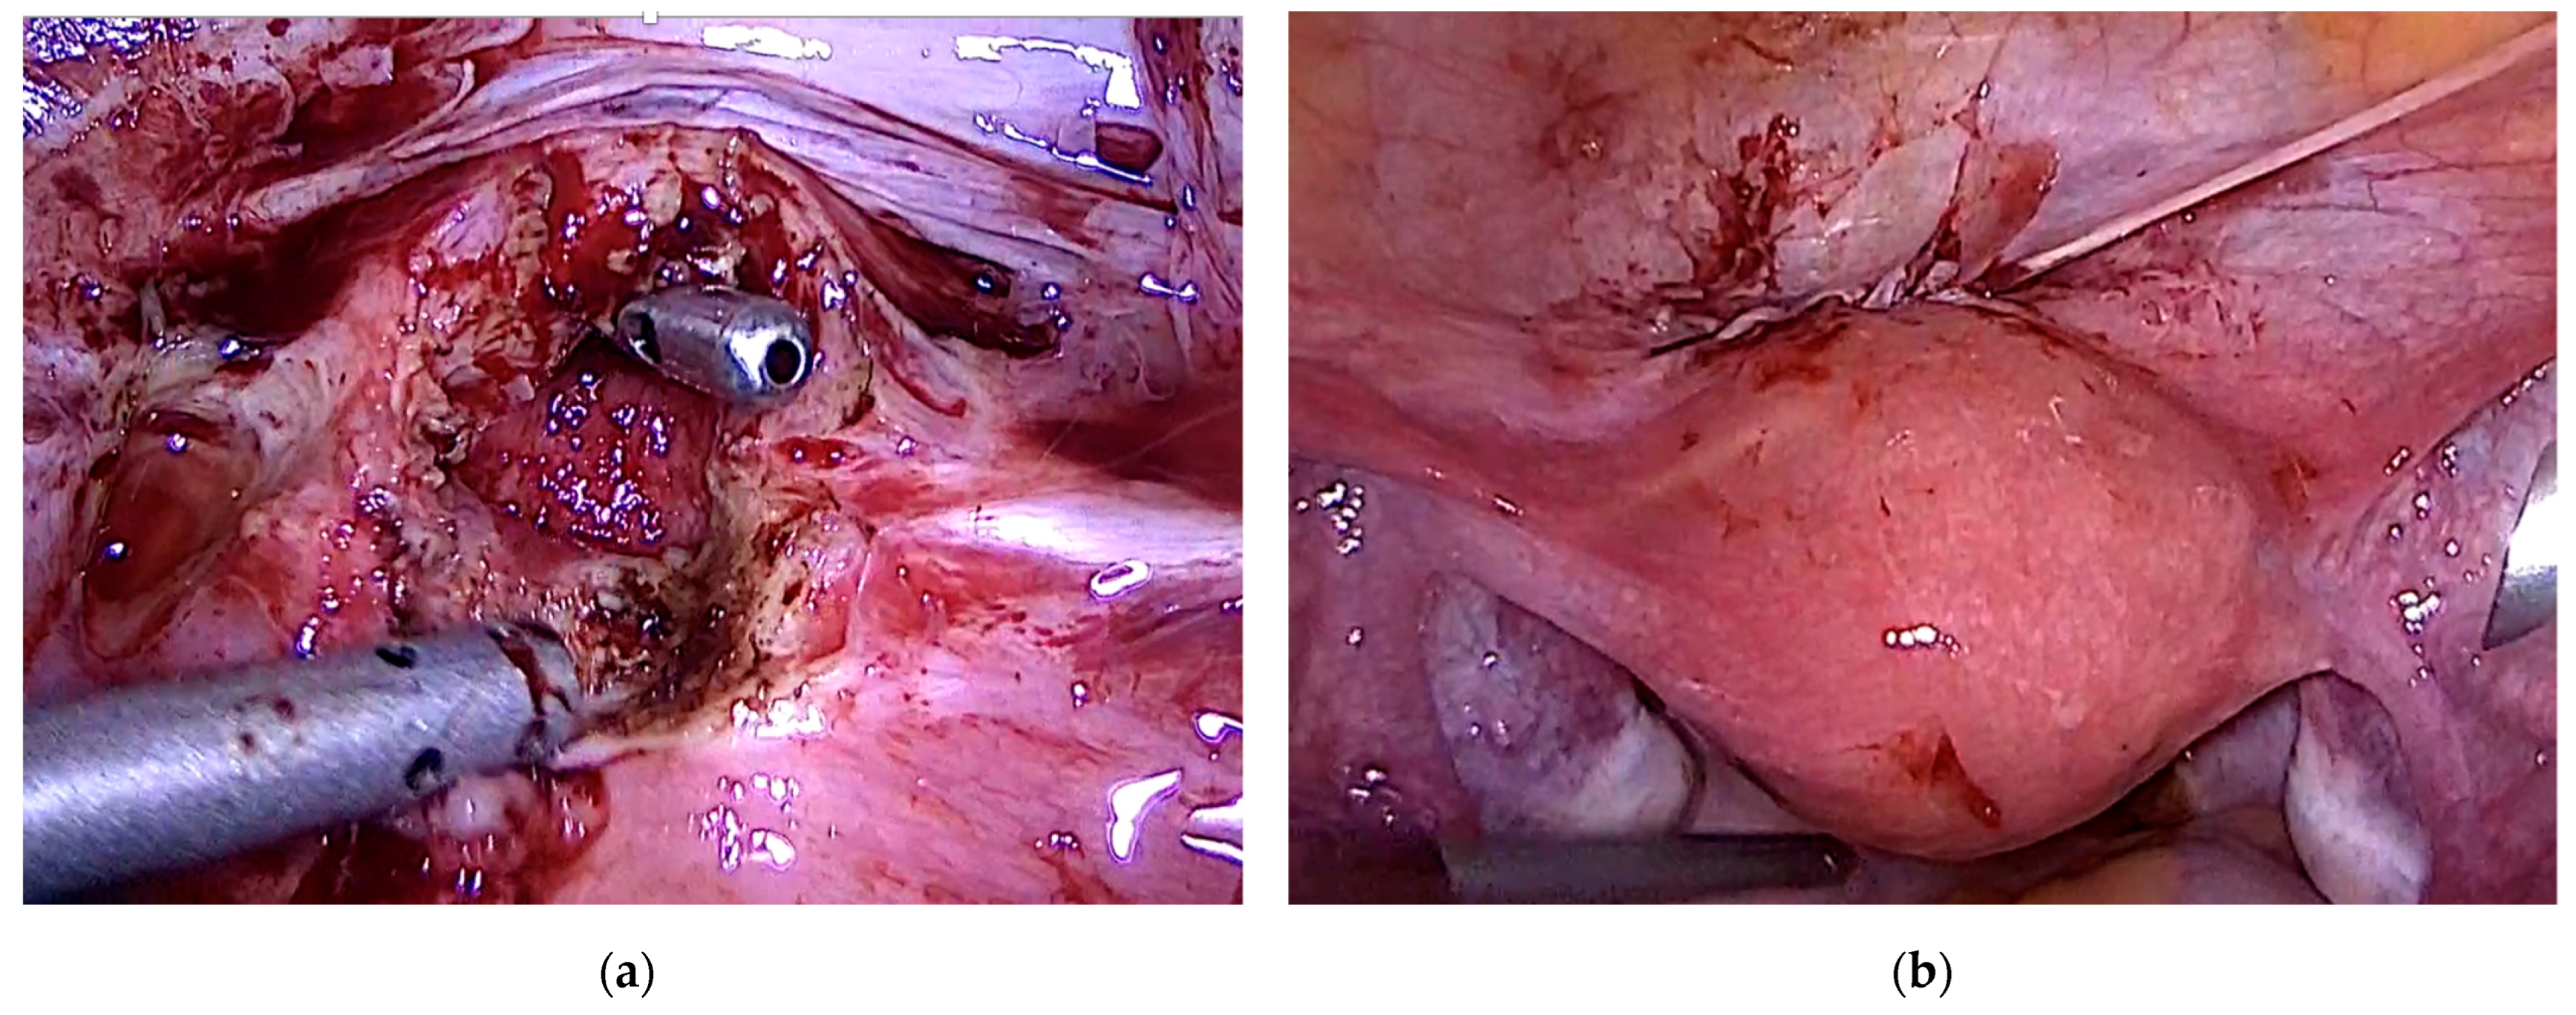

3.3. Case 3—Niche Placentation Failure—Emergency Hysterectomy